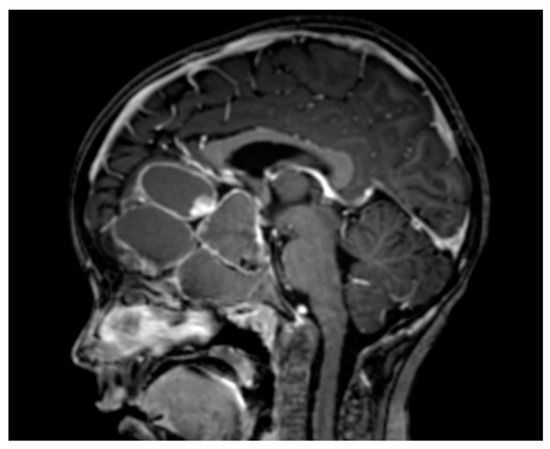

The Inflammatory Milieu of Adamantinomatous Craniopharyngioma and Its Implications for Treatment